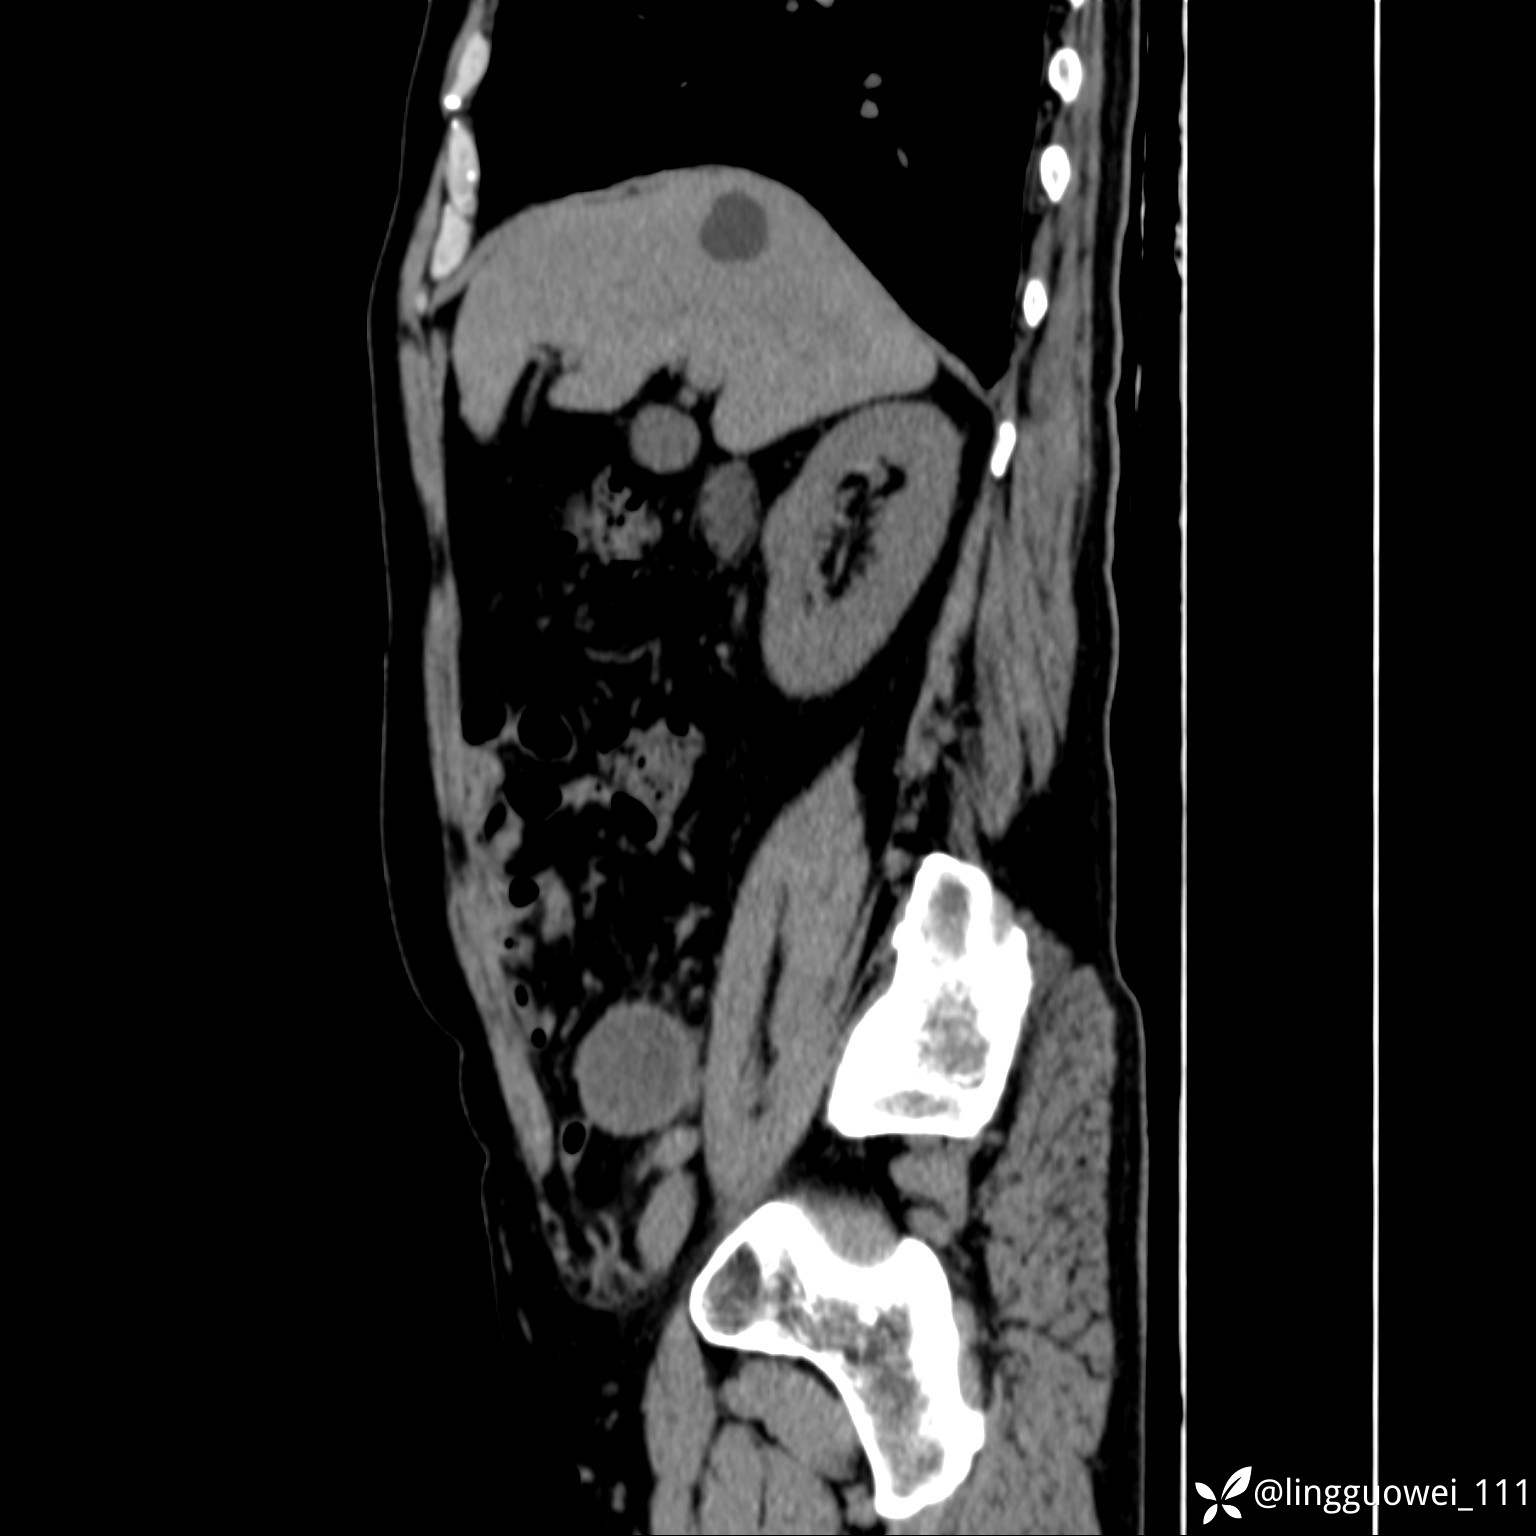

62岁,男,2天前无明显诱因出现下腹部疼痛不适,呈持续性,程度稍剧,同时伴有尿频、尿急及尿不尽感,无畏寒、发热。

平扫: